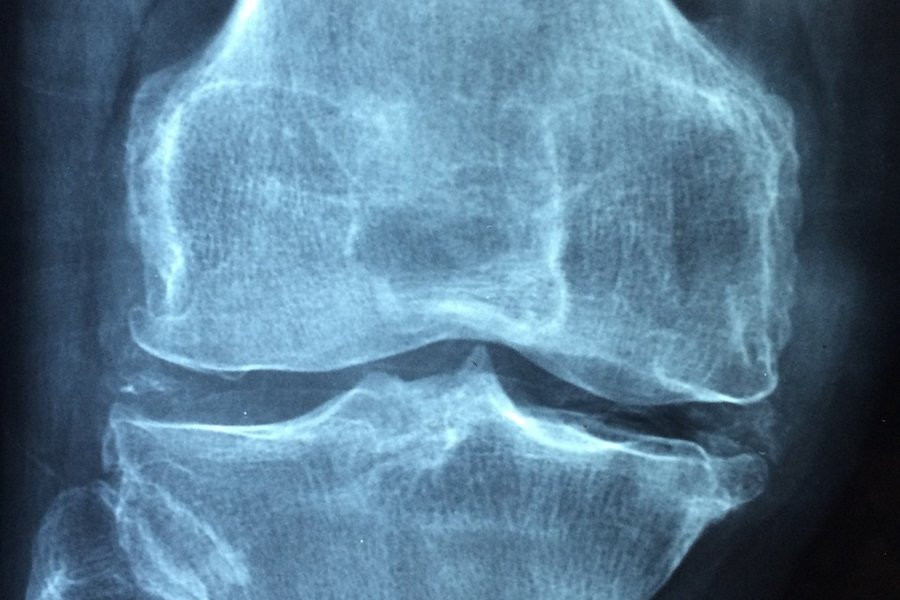

Фото из открытых источников